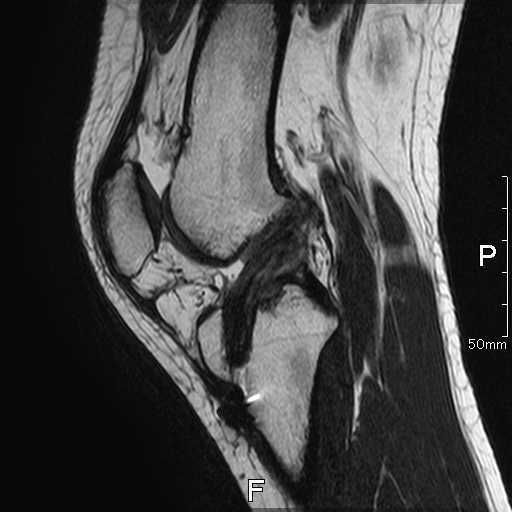

術前画像

| レントゲン | MRI |

![]() | ![]() |

| 骨傷なし、関節変形なし | ACLの連続性や緊張がみられない |